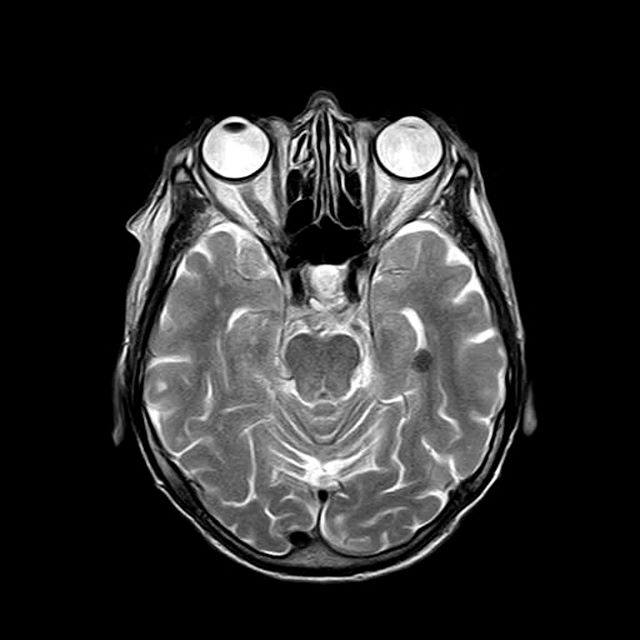

Jag skriver för närvarande oftast i StockholmsMix , där jag gör slumpvisa nedslag i Stockholms historia. Men nu har jag gått igenom diverse hälsokoller – senast alltså hjärnröntgen – (eller rättare sagt MRI = undersökning med magnetkamera) och sånt samlar jag ju gärna här i mitt ”externminne”.

Men småningom var jag äntligen på plats och fick ta av mig allt utom trosor och strumpor, samt sätta på en urtvättad sjukhusskjorta. En vänlig sköterska hjälpte mig att få in öronproppar, ovanpå det stora hörlurar och så en ”burk” runt hela huvet. (Som på bilden, men jag var utan skägg och iklädd sjukhusskjorta).